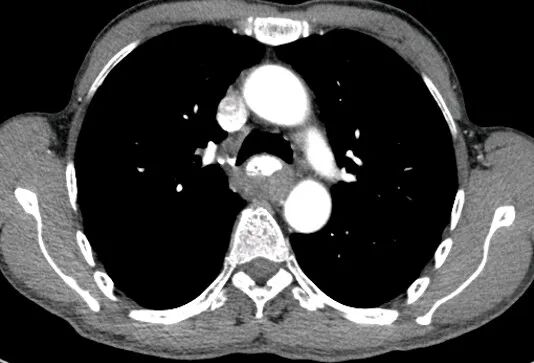

CT表现:

对于肝损伤CT能确定其存在及范围,且有非常高的特异性。肝包膜下血肿会形成新月形或半月形的低密度或等密度区,相应的肝实质会受压变平而显示肝表面的边界失去正常的弧形而变平,尤其血肿新鲜时其CT值与肝实质类似,此时注意肝表面周缘的改变亦就显得重要。

一般来讲,血肿的CT值随时间的推移而减低。在肝实质的血肿则常常显示圆形、卵圆形或星状低密度影。肝撕裂会见到单一或多发的线样低密度,边缘模糊。